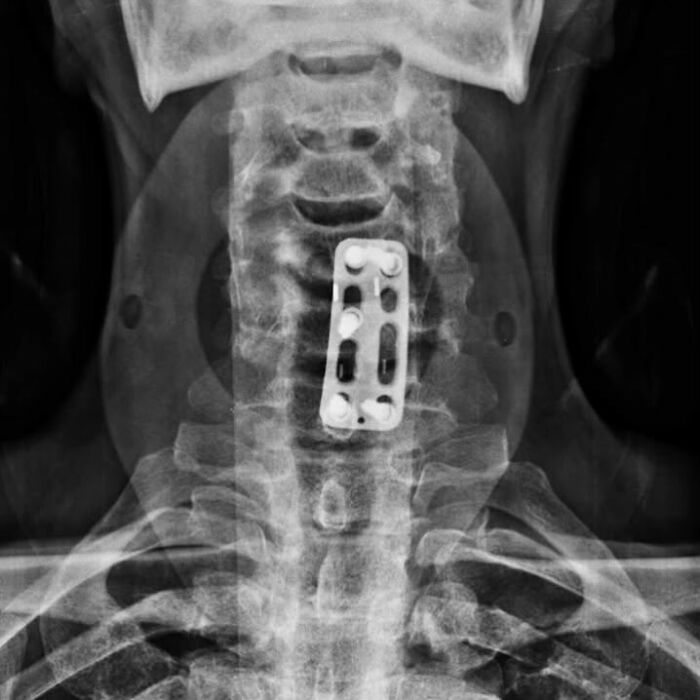

Discectomía cervical anterior y fusión